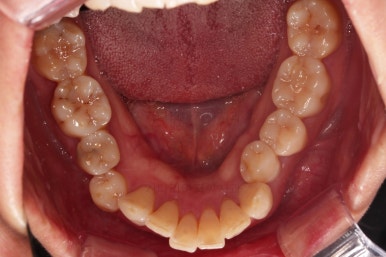

초진 시, 입안의 모습이에요.

"최근 들어 점점 틀어지고, 점점 튀어나오고, 점점 사이가 벌어져요."

성장이 끝난 성인들은 해가 갈수록 특히 아래앞니가 삐뚤어지는 것은 자연스러운데요.

이번 환자분의 말씀대로 최근에 변하가 심하게 나타난 경우는 원인이 딱 하나에요.

잇몸(치주)

흔히 풍치라고 하죠.

전반적인 잇몸이 나빠진다 -> 어금니가 씹는 힘에 버텨주지 못하고 앞으로 쓰러진다. -> 앞니가 강하게 부딪히며 아래앞니가 윗니를 앞으로 쳐낸다. -> 돌출입이 생기고, 앞니 사이 틈새가 생긴다.

앞니가 튀어나오고 틈새가 생기는 것이 결과이긴 하지만 원인은 어금니쪽 잇몸에서부터 찾아야해요.